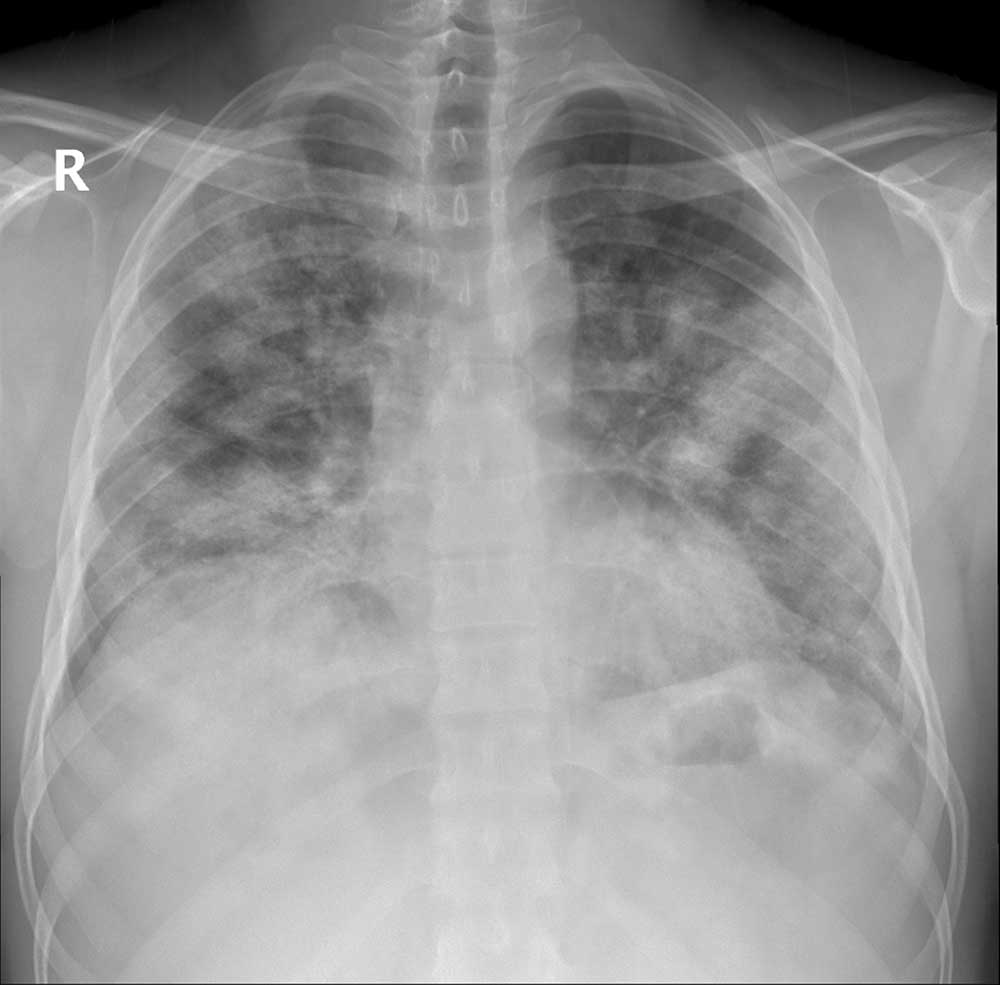

Koronavirus najviše oštećuje pluća, a tomografski snimci jasno pokazuju koliko infekcija COVID-19 oštećuje taj organ.

Neki od glavnih simptoma zaraze koronavirusom su zatajenje respiratornog trakta, otežano disanje i upala pluća, a o posljedicama koje pluća trpe od koronavirusa i brzini razvoja bolesti ponajbolje govore tomografski snimci pacijenata koje je AA dobila iz Gradske bolnice u Ankari.

Upozorivši da koronavirus oštećuje sve vitalne organe, Karalezli je rekla da je to najizraženije kod pluća, a to je pokazala i na tomografskim snimcima pluća pacijenata.

Ističući da postoje uočljive razlike između pluća zdrave osobe i pacijenta zaraženog koronavirusom, Karalezli je napravila takve snimke kako bi ljudima jasnije ukazala na posljedice infekcije COVID-19.